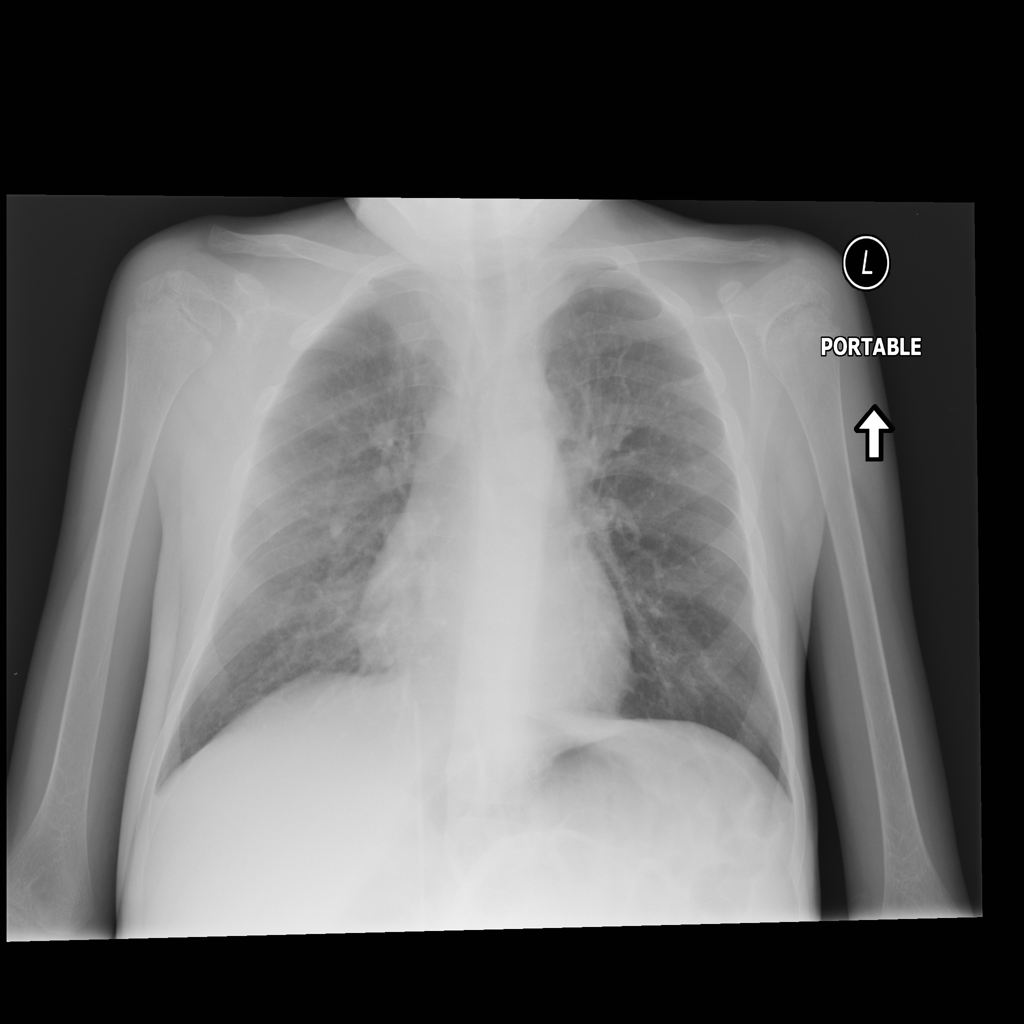

Consolidation

Consolidation refers to air-space filling that makes part of the lung appear denser on imaging.

Showing up to 90 reference images for Consolidation.

PAT-C1A7 · IMG-004Consolidation

PAT-C1A7 · IMG-004

PA